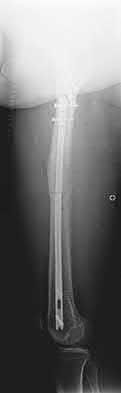

1. # A 32-year-old male sustains the injury shown in Figure A and undergoes treatment as shown in Figure B. Following placement of this implant, what is the best technique to confirm it is not too proud proximally?

The safe zone for tibial nail placement as seen on radiographs is just medial to the lateral tibial spine on the anteroposterior radiograph and immediately adjacent and anterior to the articular surface as visualized on the lateral radiograph.

Tornetta et al specifically located the safe zone for nail entry in a study using fresh frozen cadaver knees. The authors found that the safe zone for nail placement is located 9.1+/-5 millimeters lateral to the midline of the plateau and three millimeters lateral to the center of the tibial tubercle. The width of the safe zone averaged 22.9 millimeters and was as narrow as 12.6 millimeters.

The starting point of the of the nail can be best viewed on the lateral knee radiograph, an example of which is shown in Illustration A. Illustration B shows the "sweet spot" for nail insertion as defined by Tornetta.